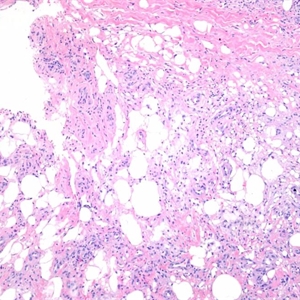

结节性红斑是一种发生于两小腿伸侧或屈侧、前臂、股部等处的红色或紫红色、慢性、炎性、结节性皮肤病。为发生于皮下组织的非特异性炎症。好发于青年女性,以春、秋两季发病多见。发病系因多种因素,如感染或药物引起的血管反应,亦可为某些疾病,如肉样瘤、麻风、淋巴瘤、结缔组织病等的一种证候。临床表现为突然发病,发疹前和发疹时可有发热、喉痛、全身不适、肌肉和关节疼痛等全身症状。皮损为鲜红色的结节,或对称性红斑,结节性损害高出皮面,大小数个结节不等,疏散分布,可有疼痛或压痛,结节不溃破,结节持续数天后,颜色由鲜红变暗红、紫红,最后呈黄绿色,终至消失,但常复发,经久不愈。

结节性红斑在中医学中属于“梅核丹”、“湿毒流注”,其病理特点为素体血分有热,外受湿邪,湿热蕴结,导致脉络阻塞、气血瘀滞等。结节性红斑按中医辨证分型可分为:风湿人络夹瘀型、湿热夹瘀型、湿毒结聚型、湿邪内蕴郁久化热型、气虚血瘀兼外感风湿型、血瘀阻络血热偏重型、热势内焚气血两燔型、肝肾不足阴虚偏重型。黄芪赤风汤主要适用于湿热夹瘀型、湿毒结聚型、湿邪内蕴郁久化热型。